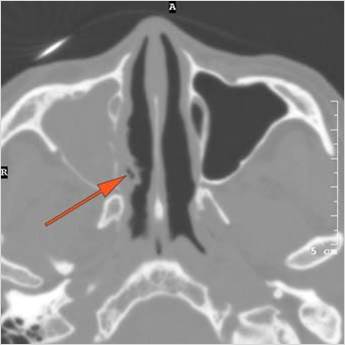

77-year-old female presenting to the emergency room with fever and headaches and possible sinusitis with possible orbital, intracranial or other complications such as cavernous sinus thrombosis.Exam

Findings are consistent with the clinical diagnosis of acute or subacute sinusitis superimposed on chronic mucocele with intracranial complications of epidural empyema along the orbital roof and early frontal lobe cerebritis.

Contact the EMS group to suggest the patient be admitted to neurosurgery service with ENT consulting.

Emergent (Action Necessary now)